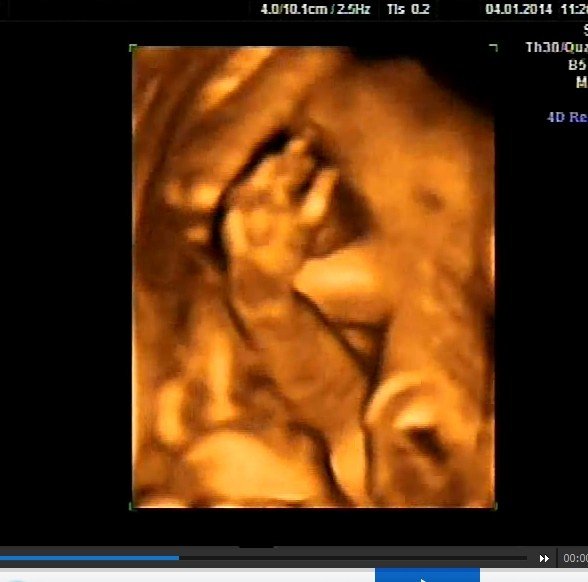

今天去做了四维彩超,请问这张图片能看的出宝宝是闺女还是儿子吗?孕25+3那么害羞,呵呵呵 点击展开 匿名用户 2014-01-04 19:33 为您推荐: 其他回答 病情分析: 可以在怀孕4个月做B超检查的,不过现在国家是禁止性别鉴定的,要顺其自然,男女一样。 指导意见: 现在主要是增加全面的营养,保持良好的心情,合理的饮食,多吃瓜果和蔬菜,粗细搭配,安心养胎。 衡夏兰_smlN 2014-01-04 20:19 相关问题 四维彩超图片 看看我这大闺女怎么样 还有六十多天就见到我家第二个宝贝了 真的好奇是女宝宝还是男宝宝 有儿子了真心想下一个是闺女!不知会 做B超看着是闺女,人们看着说是儿子,我该相信谁?